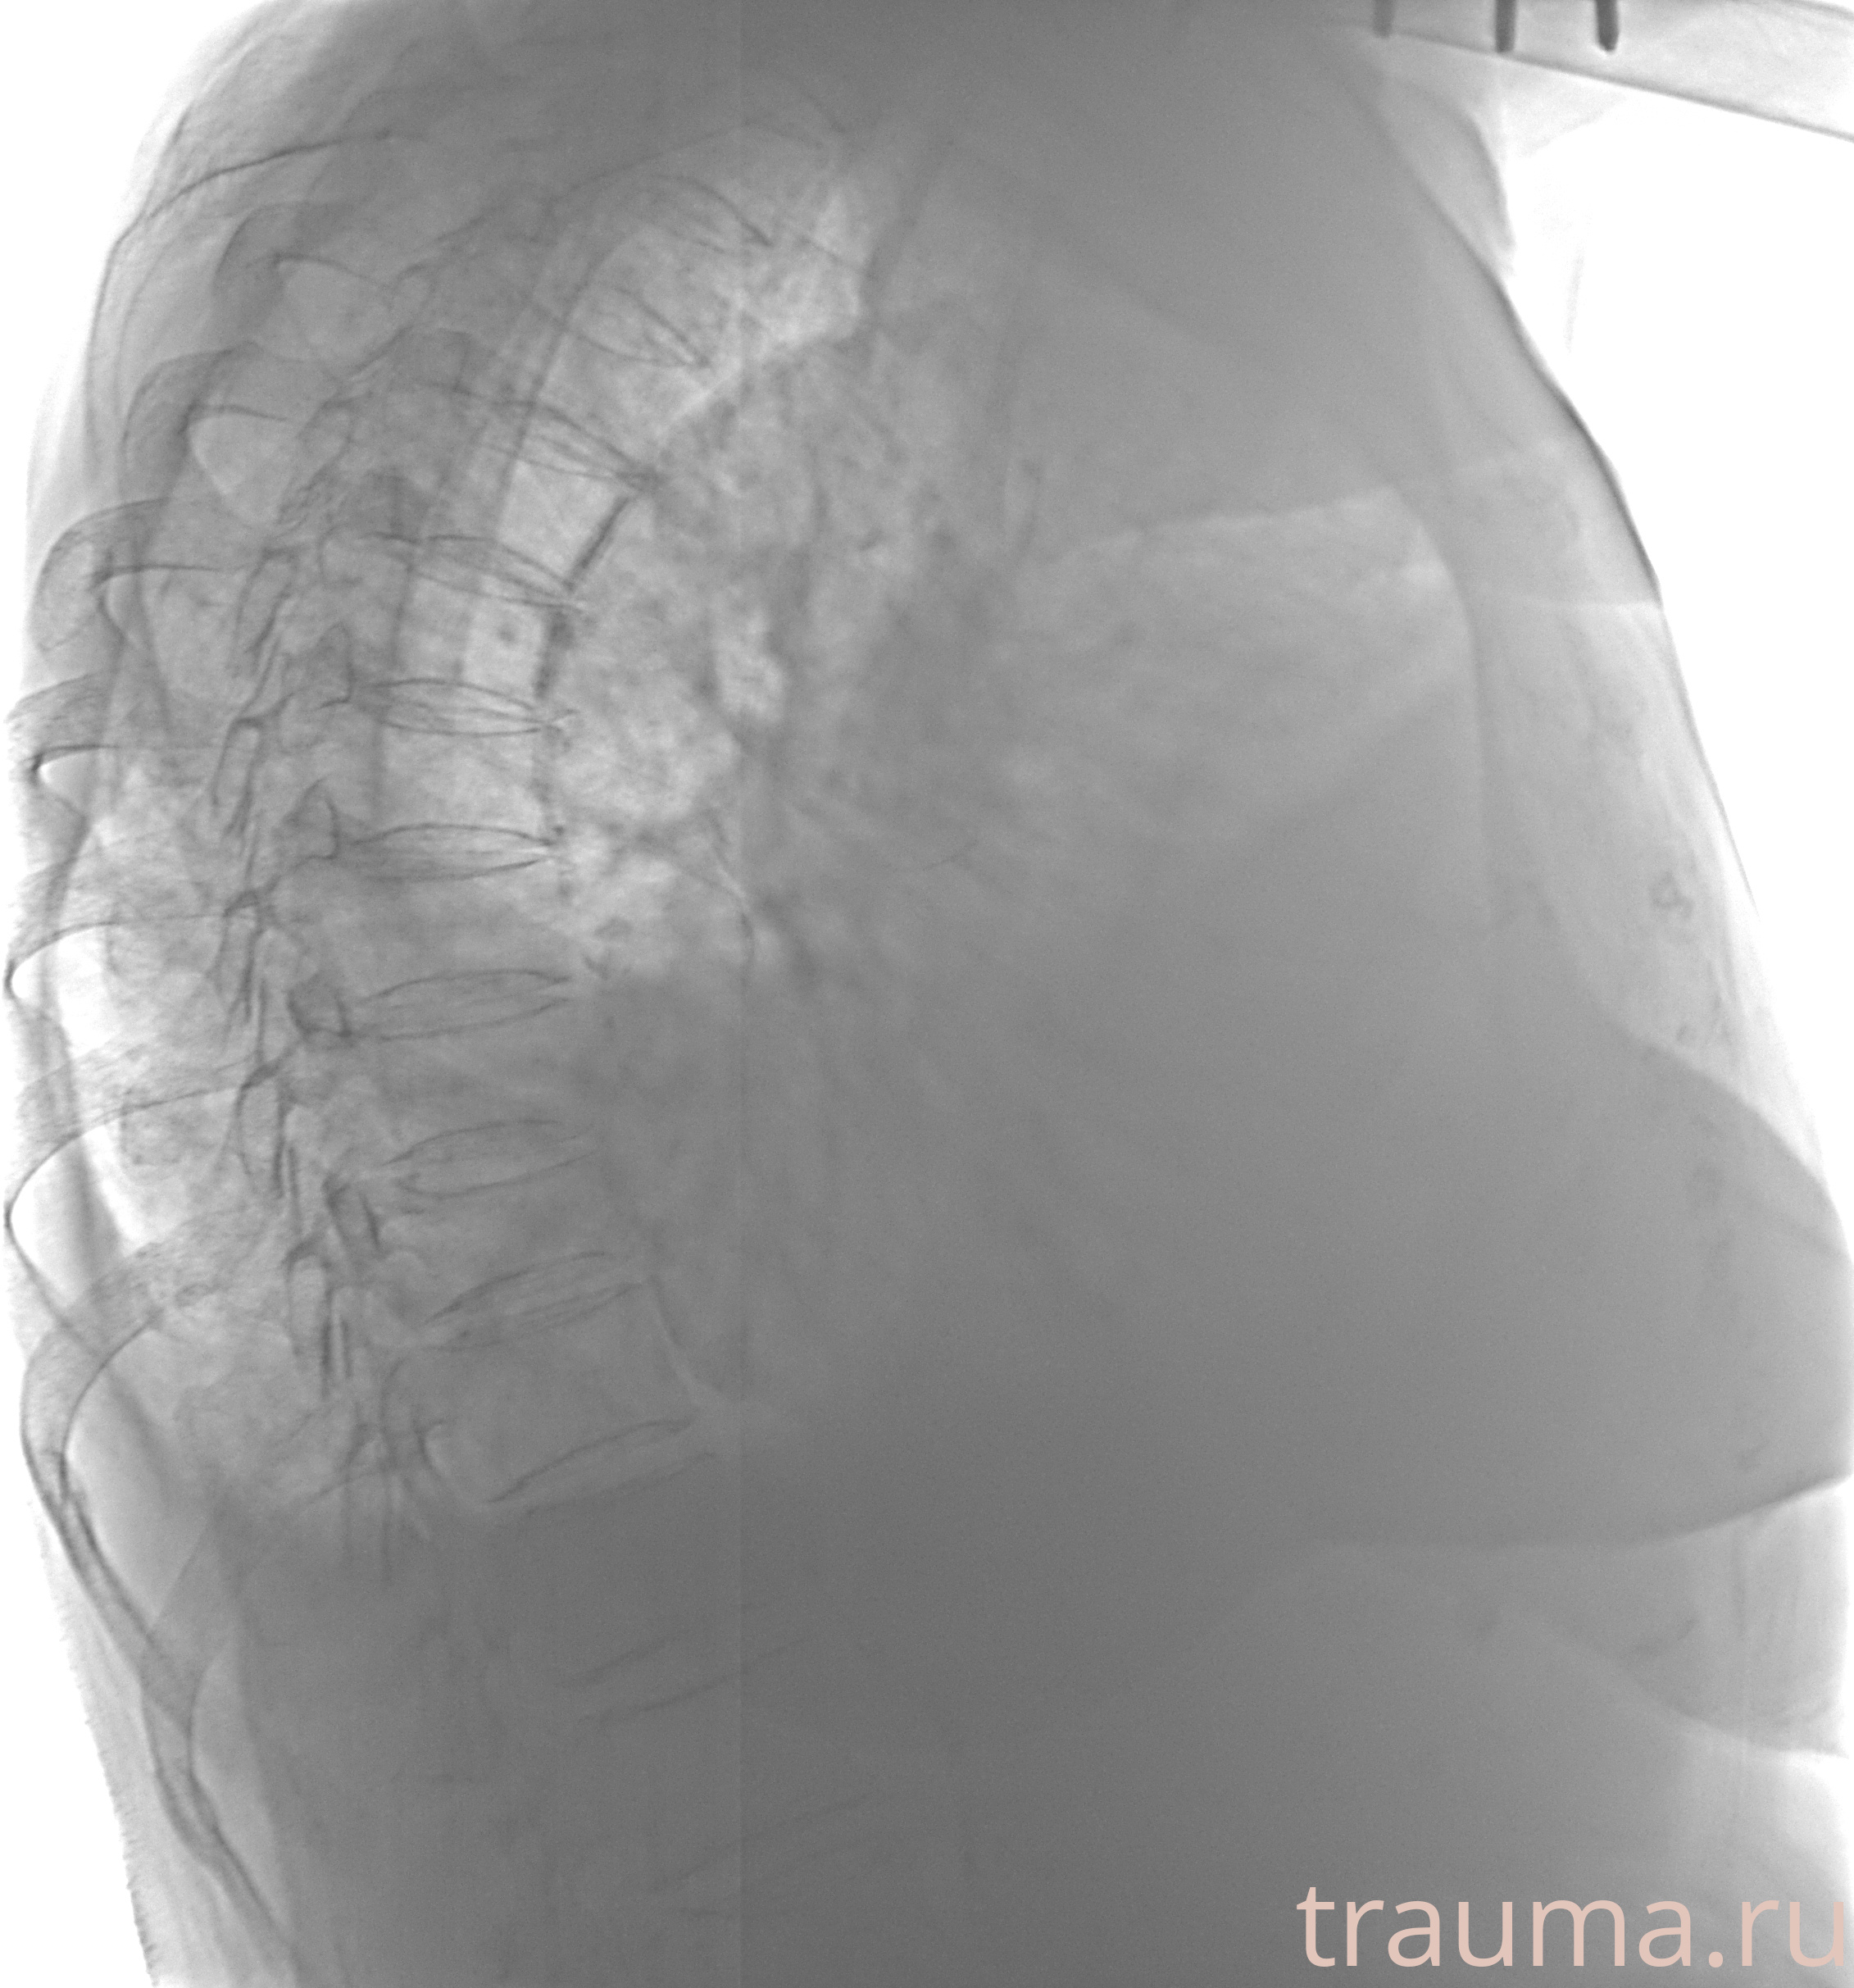

Рентгенограммы

Рентген на дому: по вашему адресу приезжает врач-рентгенолог, травматолог-ортопед с мобильным рентгеновским аппаратом, проводит диагностику травмы или заболевания, делает необходимые рентгенограммы, дает рекомендации по дальнейшему лечению. Получить качественные снимки в домашних условиях возможно благодаря уникальной методике, разработанной МосРентген Центром для института  Склифосовского

при переломе шейки бедра и пневмонии от компании МосРентген Центр - партнера Института имени Склифосовского